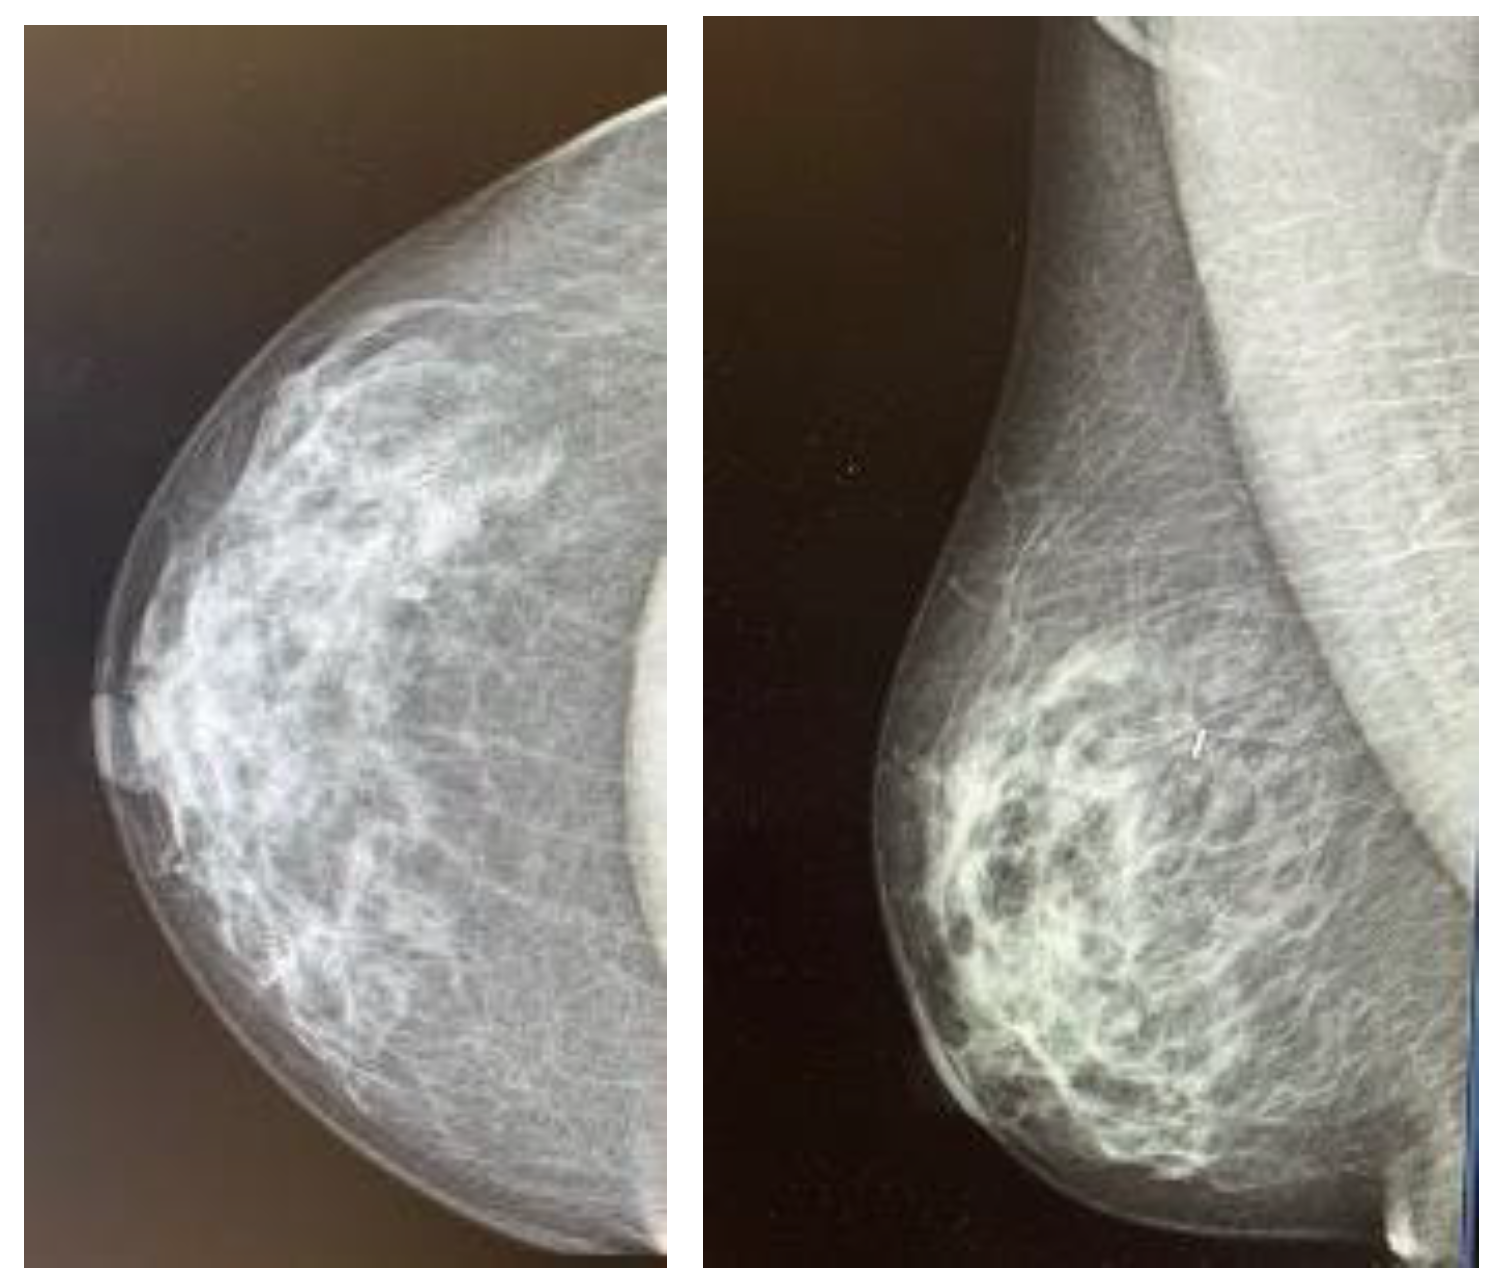

Each patient underwent a mammogram and an ultrasound at diagnosis. Magnetic resonance was performed based on the radiologist’s criteria if necessary to complete the study. Upfront treatment was decided upon the multidisciplinary committee according to international guidelines [11]. Both wires and MSs were placed by four experienced breast radiologists under ultrasound guidance, as stereo placement was not available at the time of the study. MSs were placed using local anesthesia. A control mammogram was performed after placing the wire or the MSs in all cases and could be visualized during the procedure in the operating room (Figure 1). Wires were placed on the same day of the surgery; each patient first went to the radiological room, had the wired placed, and then was taken to the surgery room or to their hospital room until the theater was available. MSs were placed independently of the surgery day, always less than 30 days before surgery, as MSs were initially approved for placement up to 30 days prior surgery (although currently, MSs have no time limit between placement and surgery). Every surgery was performed by one of the six experienced breast surgeons of the breast unit, and an informed consent form was signed before surgery [3]. MSs were intraoperatively localized using the Sentimag® probe. Every surgical specimen, including wire- and MS-guided specimens, was evaluated with a mammogram to confirm adequate excision of the lesions (Figure 2). If the mammogram of the surgical specimen showed close margins, the surgeon was informed, and the margin was extended in the same surgery.

Figure 1.

Control mammogram performed after placement of the magnetic seed.